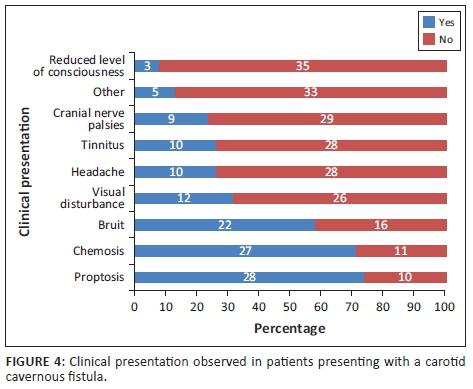

Most patients presented with orbital and/or ocular signs (92.11%). Neurological signs and symptoms were noted in more than half of the patients (60.53%). The specific symptoms and signs are presented in Figure 4. The most prevalent sign was proptosis and the least prevalent was a depressed level of consciousness. Alteration of mental state in these patients was most likely as a consequence of other injuries sustained.